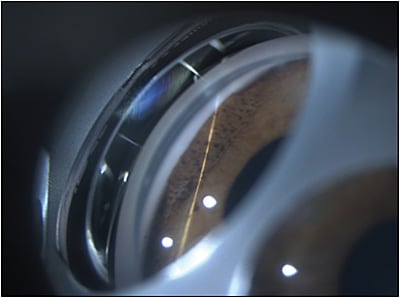

A 30-year-old female with iridocorneal endothelial syndrome (ICE) who had been followed for several years with elevated intraocular pressure (IOP) recently presented to my glaucoma clinic. She initially sought treatment 5 years ago with uncontrolled IOP in the high 30s and a Humphrey visual field with almost complete loss of the superior field and a 0.85 cup-to-disc ratio in the affected eye. Her corrected visual acuity at that time was 20/30. Her anterior-segment changes consisted of enlargement of her pupil with irregular endothelial appearance of the cornea. Gonioscopic examination revealed broad areas of peripheral anterior synechiae (Figure 1). After failure of multiple drop therapy, she was treated surgically with an Ahmed glaucoma implant (New World Medical). This initially lowered her IOP to the mid to high teens on 1 medication.